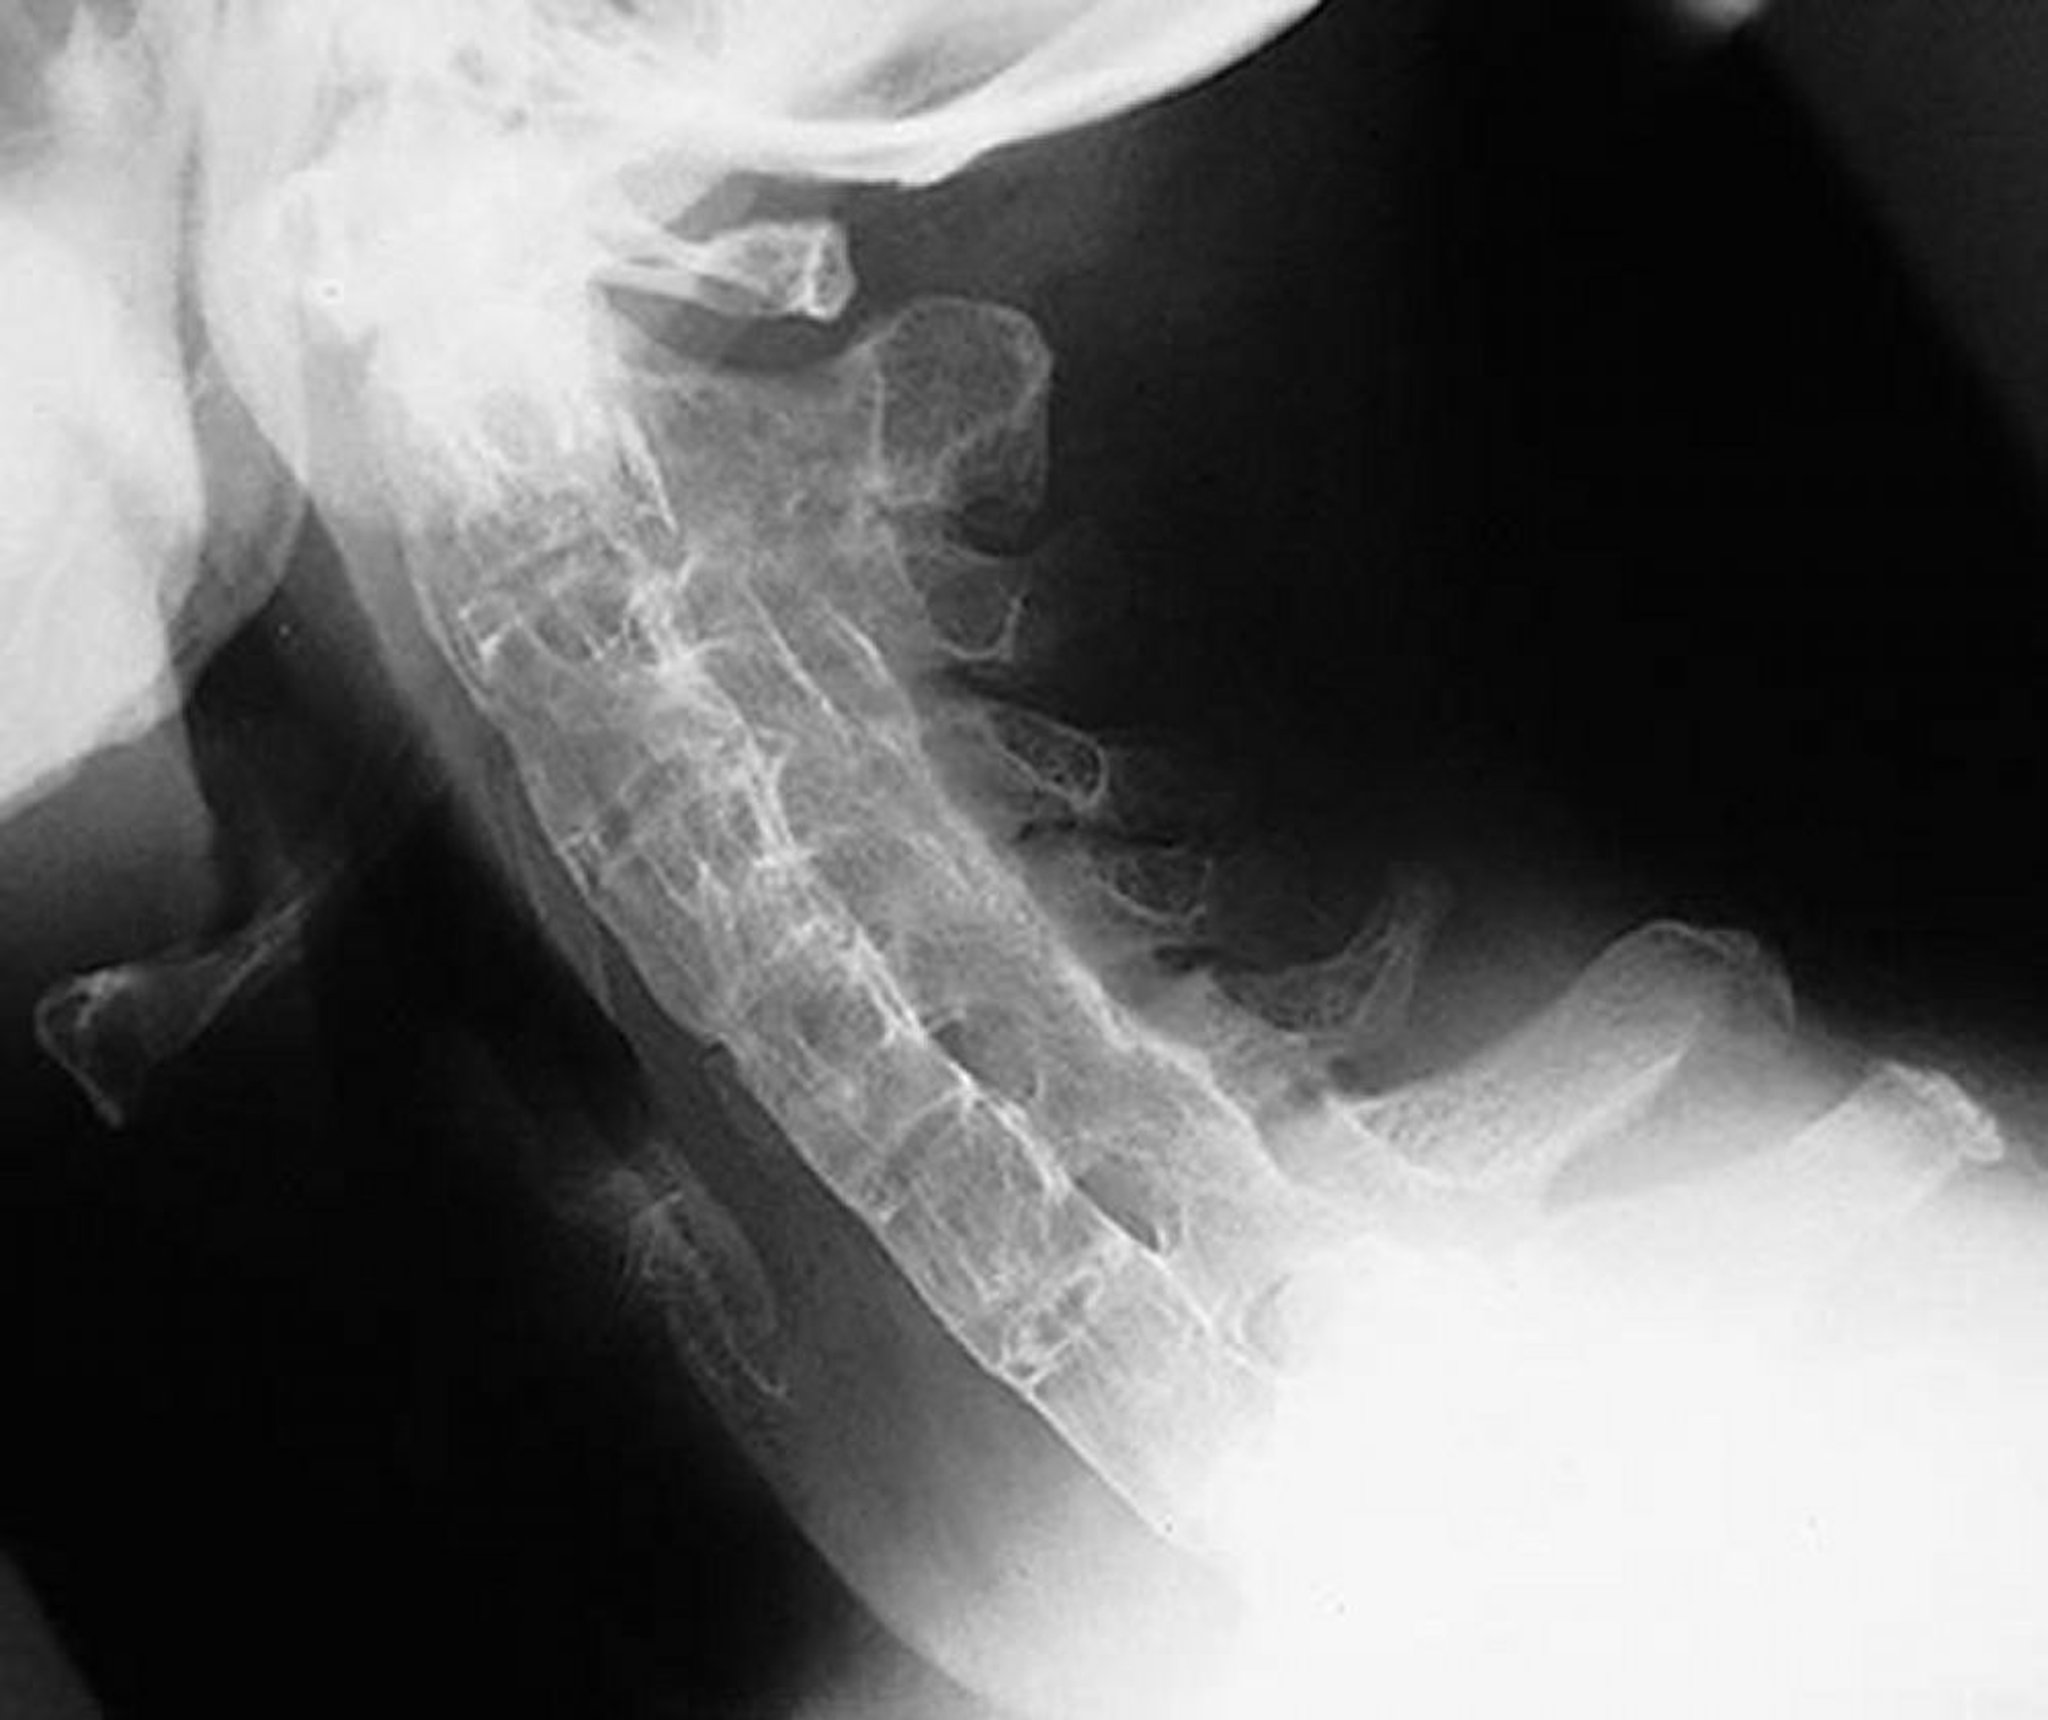

Bambuswirbelsäule bei Spondylitis ankylosans

Diese seitliche Ansicht der Halswirbelsäule zeigt eine starre Halswirbelsäule bei einem Patienten mit schwerer, langjähriger Spondylitis ankylosans. Die Wirbelsäule ist aufgrund von Syndesmophyten, verschmolzenen Facettengelenken (Apophysengelenken) und paraspinalen Bandverkalkungen vollständig ankylosiert ("Bambuswirbelsäule").